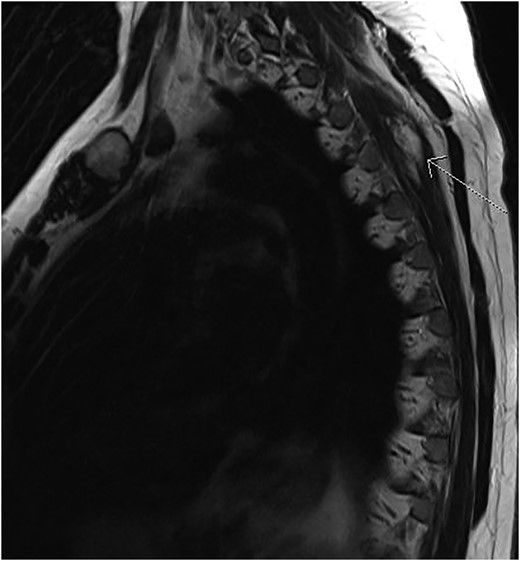

Magnetic resonance imaging (MRI) scan of her chest showed an infiltrating multi-lobulated soft tissue mass (95 mm × 40 mm × 10 mm) arising at T4 between the third and fourth left intercostal spaces without involvement of any neurovascular bundles (Fig. 1). This mass appeared to be deep to the trapezius, rhomboid major and minor muscles. Pleural thickening was noted at the same region without involvement of the lung parenchyma. The mass was non-fludeoxyglucose avid on positron emission tomography (PET)/computed tomography (CT) scan.

MRI scans shows infiltrating angiolipoma lesion in the left posterior thoracic wall, deeper to trapezius and rhomboid muscles (arrow).